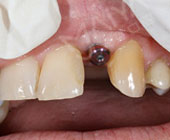

手术成功原理:借助锥形束CT判断牙槽骨骨量与骨壁厚度,重建口腔制作3D导板,微创拔除断折前牙同时借助导板完成植体植入,同期安装牙冠,形成良好的美学效果… [详细]

拔牙同时就种牙

少做手术少遭罪

避免延期骨量萎缩

不植骨更省钱